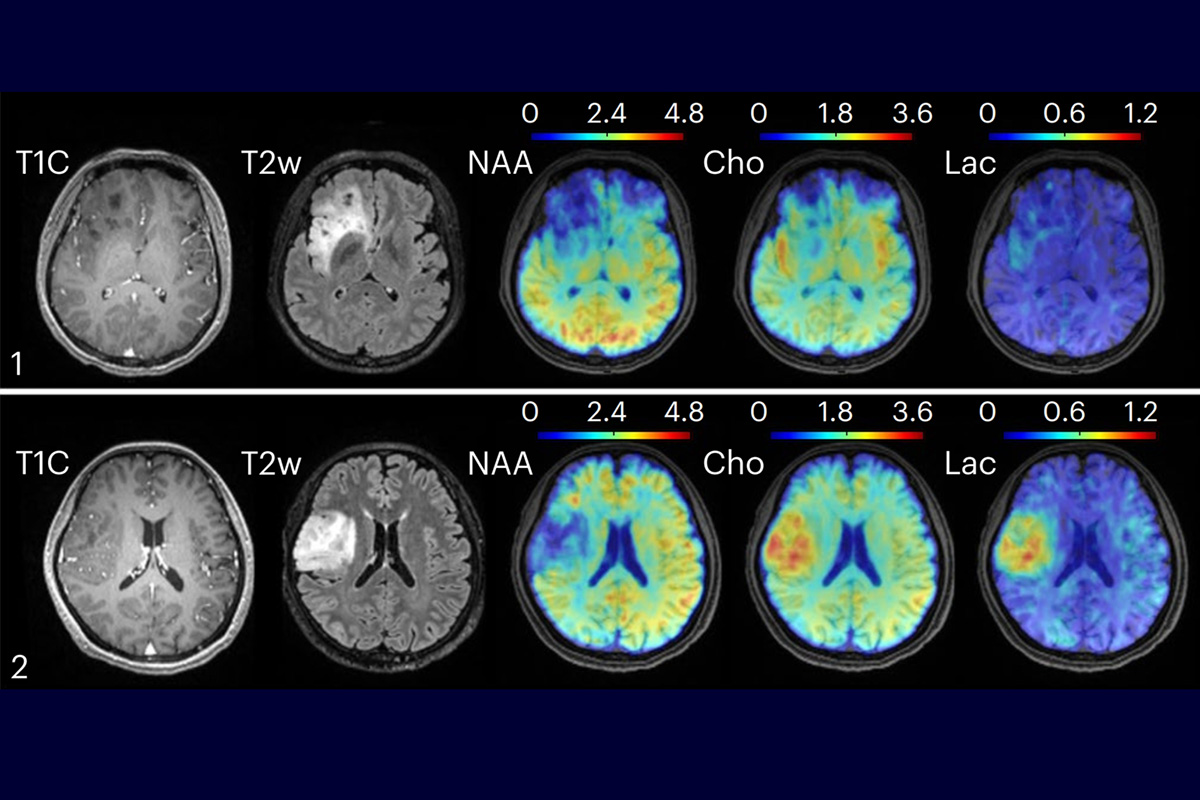

New technology combining high-speed MRI with machine learning methods for data processing found metabolic changes in oligodendroglioma brain tumors. Clinical MRI, in the left two columns, could not distinguish between tumors of grade II, top, and grade III, bottom. However, the new technique found elevated levels of choline and lactate in the grade III tumor. Image courtesy of Yibo Zhao

The researchers tested their MRSI technique on several populations. In healthy subjects, the researchers found and mapped varying metabolic and neurotransmitter activity across different brain regions, indicating that such activity is not universal. In patients with brain tumors, the researchers found metabolic alterations, such as elevated choline and lactate, in tumors of different grades — even when the tumors appeared identical on clinical MRI images. In subjects with multiple sclerosis, the technique detected molecular changes associated with neuroinflammatory response and reduced neuronal activity up to 70 days before changes become visible on clinical MRI images, the researchers report.